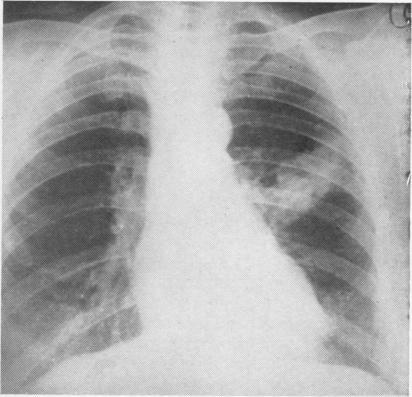

Localized "alveolar cell" tumour with bronchial involvement.